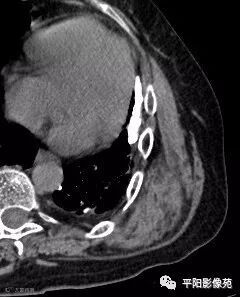

影像表现

两例患者均为左侧肩胛下实性软组织肿块,边缘模糊,质软,内为肌肉样密度及脂肪密度,以肌肉样密度为主。

CT:边界模糊,与肌肉相似的密度,病变内部可见点状、条状脂肪密度,增强扫描轻度强化或无强化。